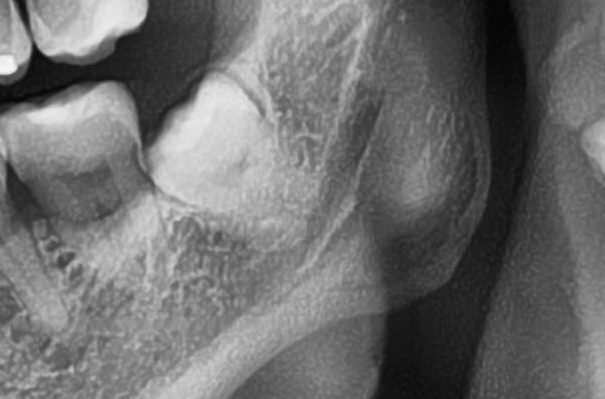

次にパノラマ写真を撮影してみると、左下の親知らずは歯ぐきの奥で生えているのが確認できました。